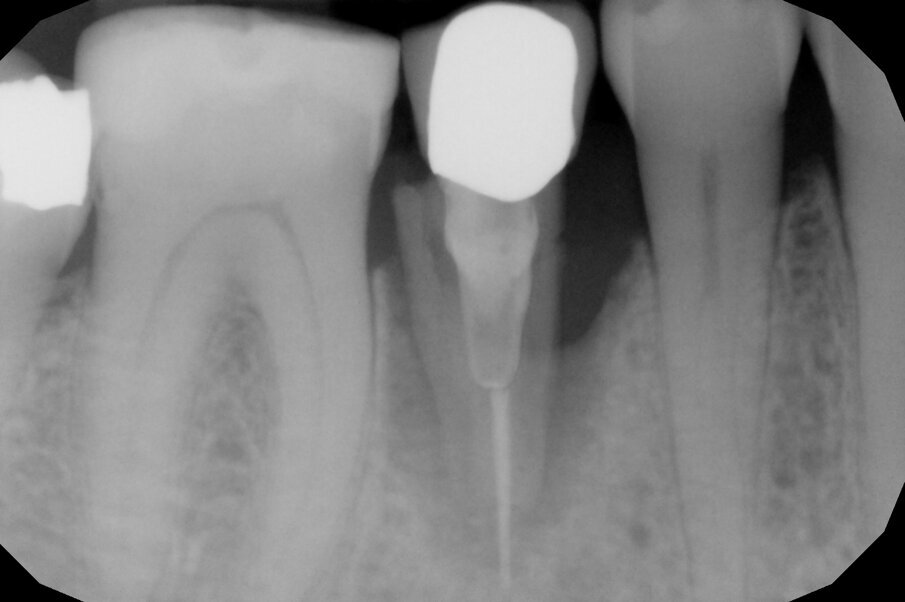

In questo caso clinico la difficoltà consisteva nel fatto che si è resa necessaria l’estrazione della metà mesiale della radice fratturata e quindi nel far compiere al frammento radicolare rimasto un movimento diagonale per mezzo del quale la porzione distale rimasta con il legamento parodontale avrebbe permesso una corretta rigenerazione tissutale ossea come indicato in rosso nell’immagine radiografica.

Per ottenere questo risultato nel gennaio 2021 è stato ancorato un segmento di arco in acciaio a sezione quadrata 0.021” x 0.025” agli elementi 4.4 e 4.6 per mezzo di composito. Il segmento è servito da ancoraggio per una molla con forza di trazione 150 g in posizione obliqua in senso disto-mesiale.

L’estrusione completa del frammento ha richiesto un tempo di 6 mesi, durante i quali è stata modificata più volte l’inclinazione della molla per evitare che il movimento diventasse ortogonale al segmento e mantenere la traiettoria prevista. Così facendo, è stato possibile rigenerare naturalmente l’intero alveolo e inserire, dopo 3 mesi di ulteriore maturazione del tessuto, in un contesto osseo ideale e perfettamente rigenerato un impianto Syra (Sweden & Martina) di diametro 4.25 mm e lungo 11 mm.